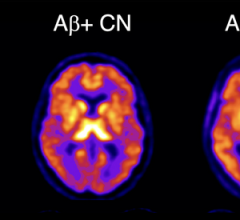

July 16, 2025 — Artificial intelligence can improve diagnostic consistency and reduce false-positives in prostate cancer ...